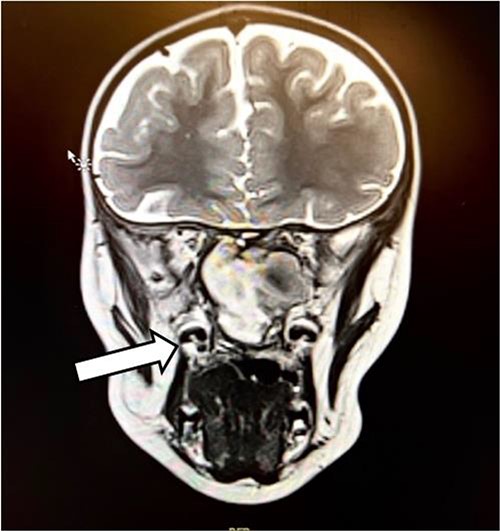

In the operating room (OR), examination under general anesthesia (GA) using a rigid nasal endoscope showed a heterogenous mass in the posterior nasal septum destructing the vomer, rostrum, and sphenoid wing. The mass was evacuated by the EEA while using the navigation system. The evacuation extended posteriorly to the sphenoid sinus, laterally to the sphenoid wing, and superiorly to the skull base (Figs 3 and 4). Lastly, Doyle nasal splints were inserted bilaterally to prevent re-accumulation of a hematoma (Fig. 5). Post-operatively, NovoSeven was administered for optimization. The patient was discharged in stable condition, and 10 days later underwent removal of the splints in the OR under GA. He followed up post-operatively at the otolaryngology clinic and was doing well, with no further complaints of epistaxis.